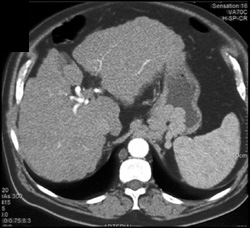

Gastric Cancer